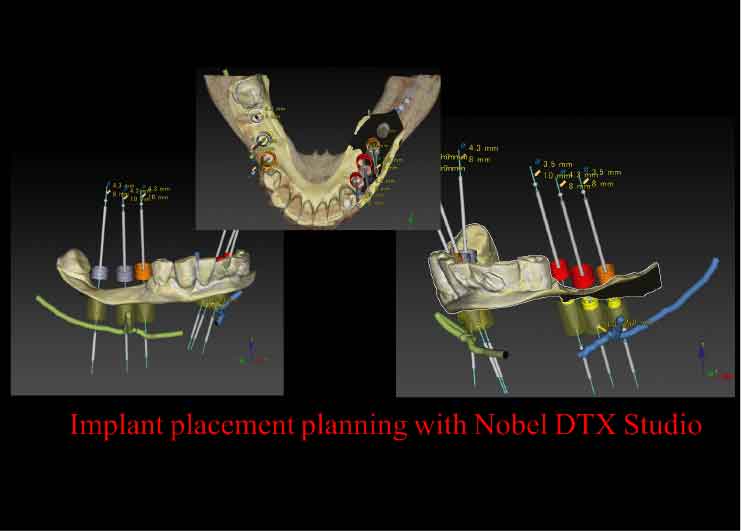

Case2. 68歳男性

下歯槽神経近くにインプラントを埋入したケース。

歯を失った下あごの骨が大きく吸収し、下歯槽神経の出入り口であるオトガイ孔が表面に近い部分に出てきています。そこで、X-ガイド使用により、下歯槽神経を避けた手術を行いました。

CTスキャンを撮影後、下歯槽神経の位置を明示した3D模型を作製。

DTX Studioで、下歯槽神経の位置とインプラントの埋入方向、深度を詳細に検討し、神経にダメージを与えないインプラントの位置をシミュレーション、X-ガイドによるナビゲーション手術を行いました。

DTX Studioで、下歯槽神経の位置とインプラントの埋入方向、深度を詳細に検討し、神経にダメージを与えないインプラントの位置をシミュレーション、X-ガイドによるナビゲーション手術を行いました。